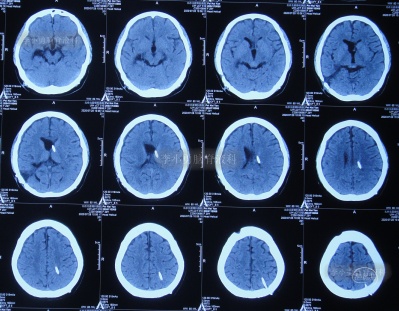

入院治疗11天即2020年4月22日, 查头颅CT示脑室缩小,出血消失(图-20),头晕呕吐消失。

图-20:2020年4月22日头颅CT

入院治疗18天即2020年4月29日,进行了脑室腹壁外引流术,头颅CT示脑室缩小,脑室内仅有1根管(图-21)。

图-21:2020年4月29日头颅CT

入院治疗100天即2020年7月20日,进行了脑室腹腔分流术。术后当天查头颅CT示脑室分流术后状态(图-23)。

图-23:2020年7月20日头颅CT

入院治疗109天即2020年7月29日康复出院,出院时:头晕呕吐已完全消失2月余,视物不清也变正常,睡眠也变好(图-24);出院时头颅CT示无异常(图-25)。

图-25:出院时头颅CT